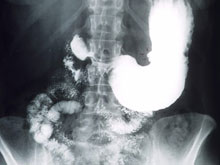

НОВОСТИ. Пищеварительная система

Уникальные таблетки из биокожи помогут победить язву желудка

Разработка принадлежит исследователям из Оренбургского государственного университета. По словам специалистов, новая таблетка с гилауроновой кислотой может также помочь при ожогах и трофических язвах. Ученые впервые рассказали о своем изобретении в 2008 году. Потом в ходе исследований специалистам удалось создать аналог человеческой кожи, пишут "MED Новости".

Материал, используемый исследователями, называется G-Derm. Его особенностью является улучшенная адгезия (сцепление). В этом году материал протестировали на крысах. В следующем году начнутся клинические испытания. Ученые надеются: новые таблетки изменят жизнь людей, страдающих от язвы.